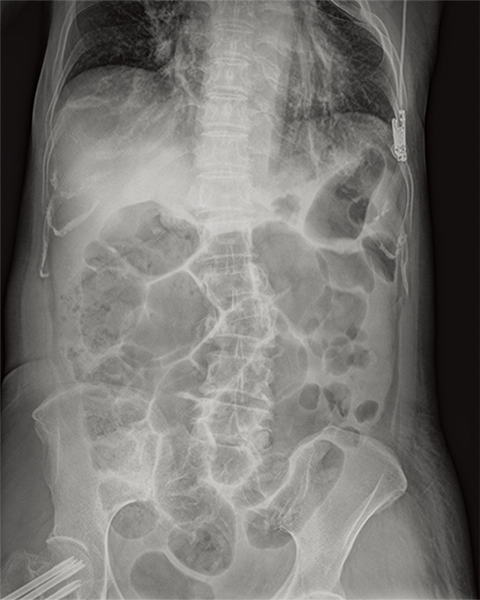

Multiple body parts supported

Cervical Spine

Thoracic Spine

Lumber Spine

Dynamic Visualization II

Optimizes image quality using latest Exposure Data Recognizer

Advanced recognition algorithms using automatic  calculations of estimated 3D image data, identify the body part required and adjusts contrast, density and enhancement for optimised image display. (Option)